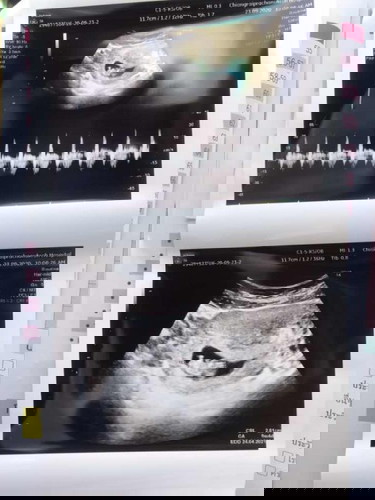

ซาวครั้งที่2คะ เจอน้องแล้ว

9w4d ทีมเดือน เมษา 64 คะ

อายุครรไล่เลี่ยกันเลยค่ะ9w4dถ้าแม่ไปซาวเองคงได้เห็นเจ้าตัวเล็กแบบนี้แน่ๆ❤️1พค64